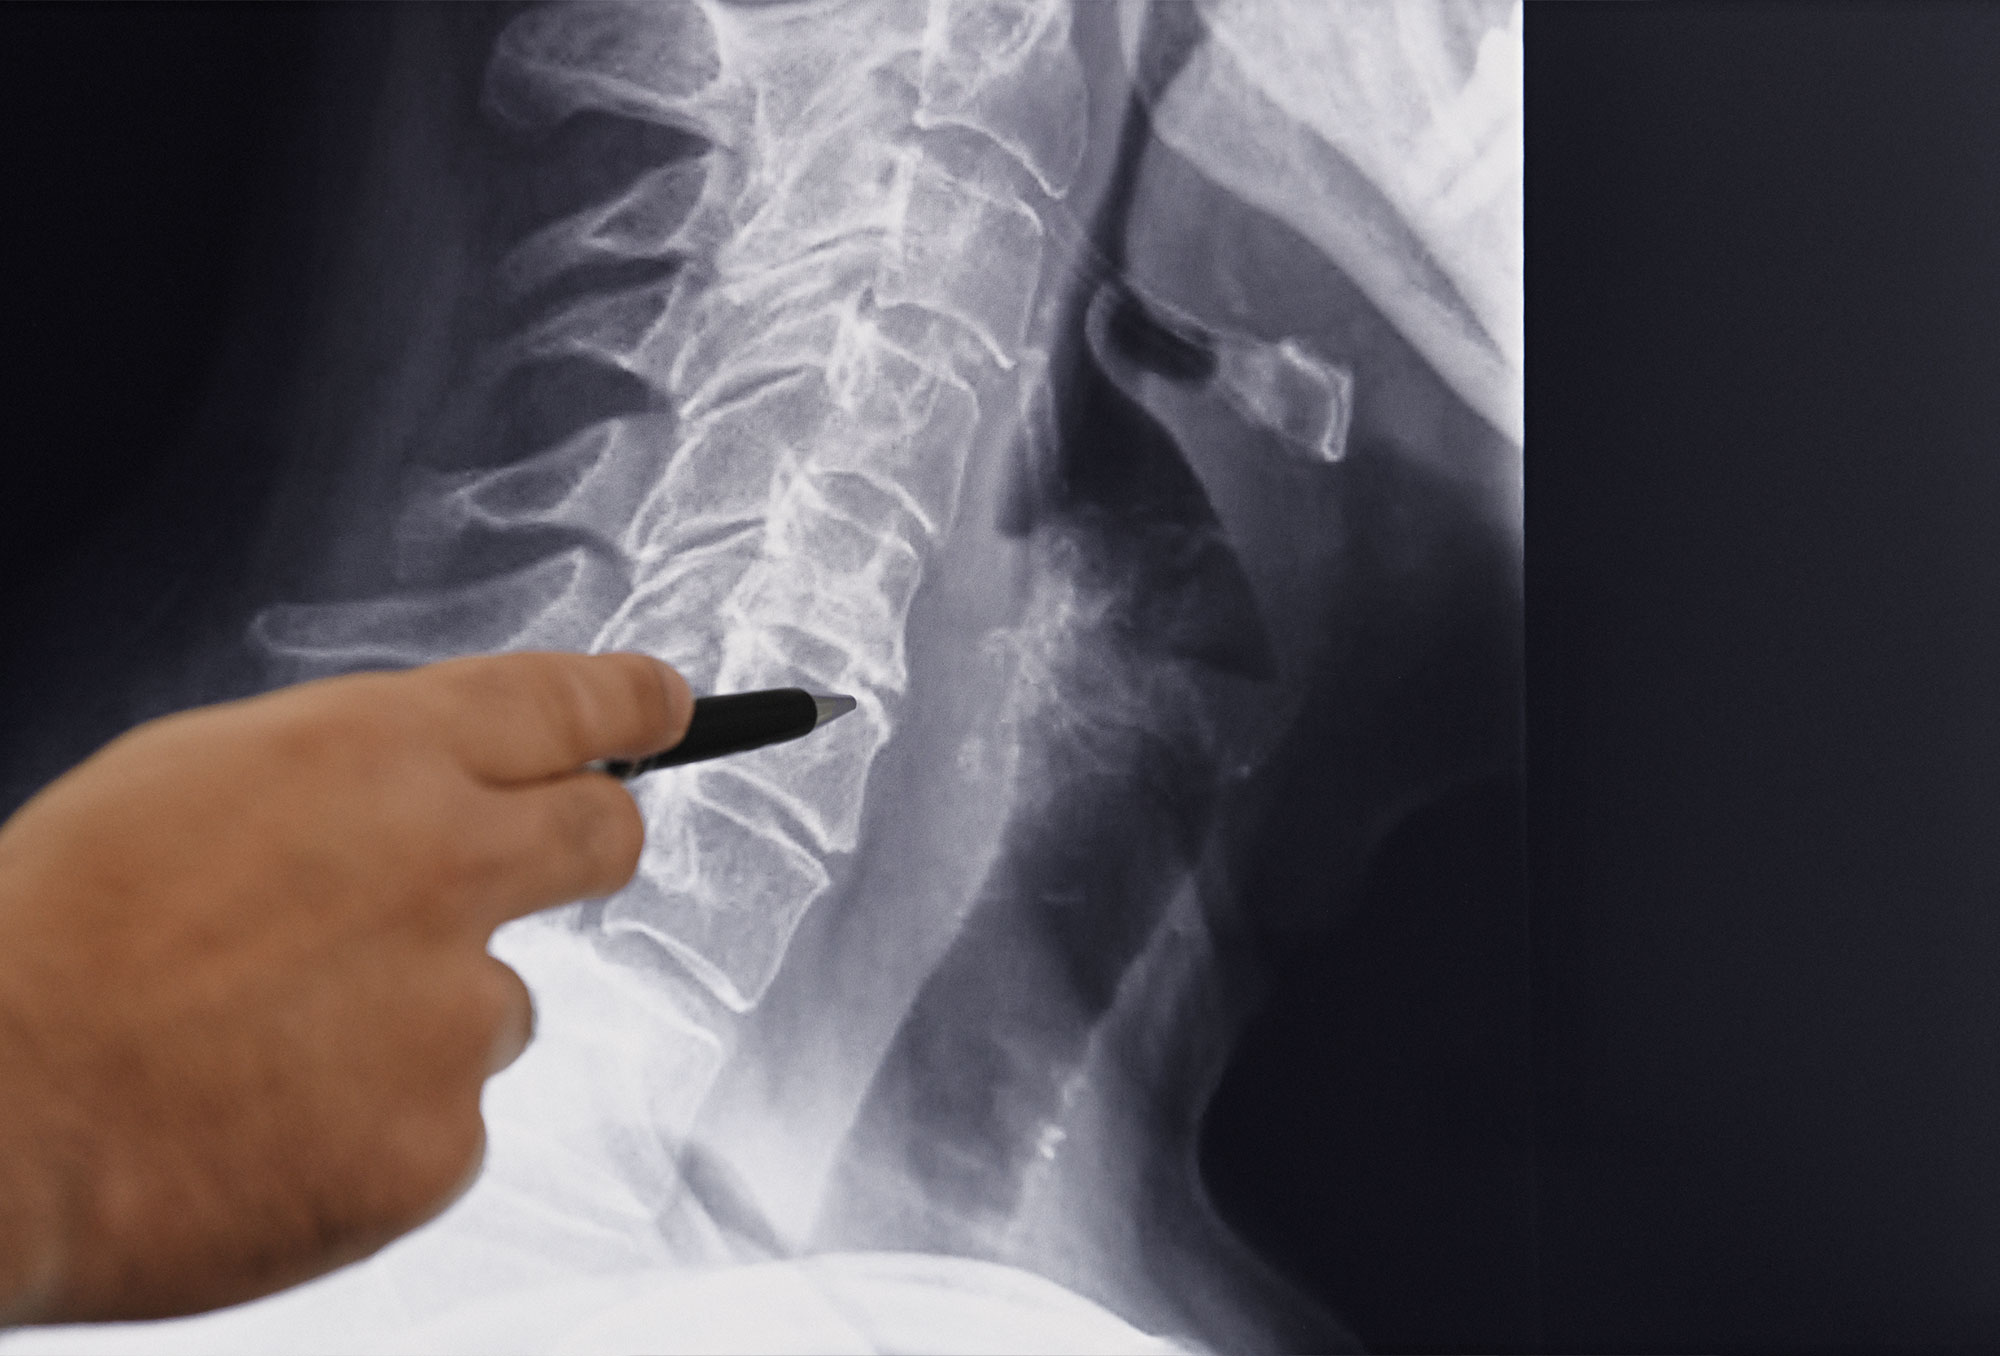

Die Wirbelsäule stabilisiert den Rücken durch Wirbel, Bandscheiben, Rückenmark, Bänder und Muskeln. Störungen können Rückenschmerzen durch Verschleiß, Veränderungen oder Stress verursachen. Wir behandeln Bandscheibenvorfälle, Spinalkanalstenosen und Wirbelkörperbrüche mit modernen Verfahren. Unser Ziel ist eine massgeschneiderte Therapie für Ihre Beschwerden.